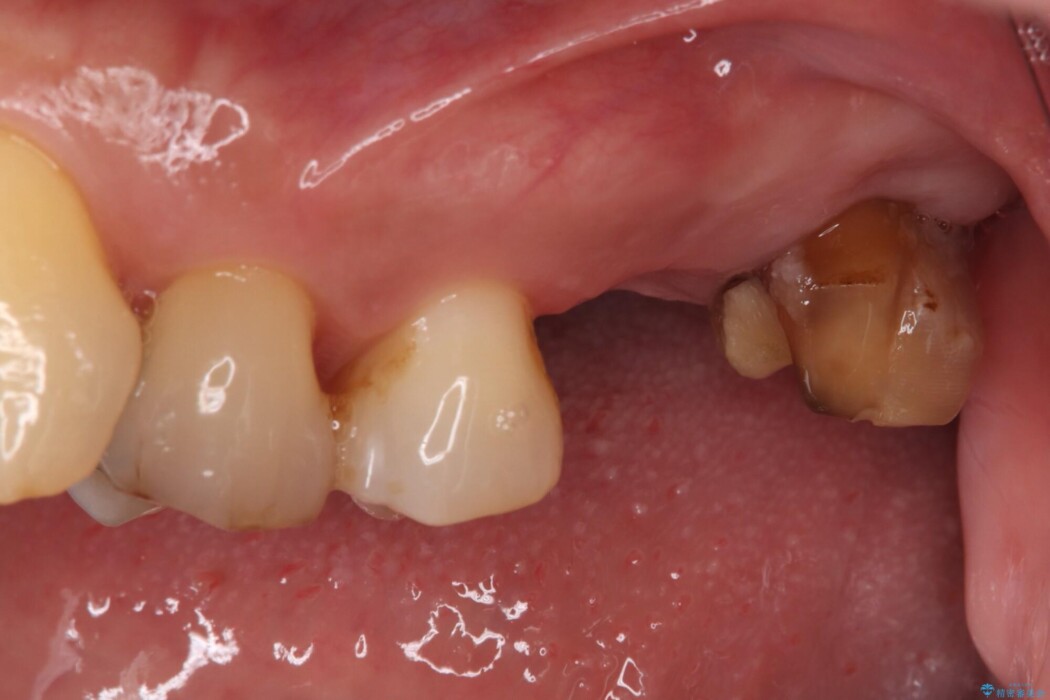

過去に治療を中断し、そのままにしていた左上奥歯の治療をしたいとご来院されました。

精密検査の結果、治療を中断していた左上7番は重度の虫歯や歯周組織の崩壊により保存が難しい状態でした。

6番も歯を失ってから時間が経っていたため、奥歯でしっかりと噛むことができない状態でした。